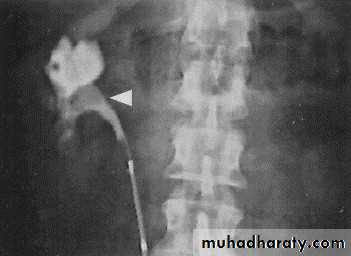

Acutely obstructed kidney shows a dense nephrogram (dense opacification of the renal parenchyma).

excretion of contrast (opacification of the collecting system which may take many hours), then the level and degree of obstruction can be determined as dilated pelvi-caliceal system and ureter are followed down to the point of obstruction (point of hold up).

Pyeloxinus reflux may result from rupture of a fornix precipitated by contrast-induced diuresis superimposed on the increased hydrostatic pressure of an obstructed pelvicaliceal system. Urine and contrast extravasate into the renal sinus and perirenal space